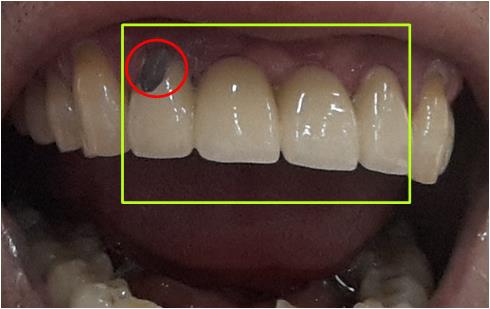

÷ºÎ»çÁøÀº ÀúÀÇ Ä¡¾Æ »çÁøÀÔ´Ï´Ù.

³ë¶õ»ö¾ÈÀÇ °³ Ä¡¾Æ´Â ÀÇÄ¡ÀÔ´Ï´Ù.

2°³ÀÇ Ä¡±ÙÀ» ÀÌ¿ëÇÏ¿© 2°³¸¦ ºê¸´ÁöÇüÀ¸·Î ¿¬°áµÇ¾î ÀÖ½À´Ï´Ù.

Àû»ö¿øÀ¸·Î Ç¥½ÃµÈ ºÎºÐÀº ÀϺΰ¡ 꺠Áø ºÎºÐÀÔ´Ï´Ù.

¹®ÀÇÇØÁֽŠºÎºÐÀÇ Ä¡·á¹æ¹ý¿¡´Â

ù¹øÂ°·Î 4°³ÀÇ ºê¸´Áö¸¦ ´Ù½Ã ÇÏ´Â ¹æ¹ý°ú

µÎ¹øÂ°·Î ±úÁøºÎºÐ¸¸ ¼öÁ¤ÇÏ¿© ¶ó¹Ì³×ÀÌÆ®Ã³·³ ÀºÎºÐÀ» ºÙÀÌ´Â ¹æ¹ýÀÌ ÀÖ½À´Ï´Ù.

±â°£Àº ¾à 2ÁÖÁ¤µµ °É¸®¸ç, 2Á־ȿ¡ 2¹ø¸¸ ³»¿øÇØ ÁÖ½Ã¸é µË´Ï´Ù.

ÇÏÁö¸¸ »çÁø»óÀ¸·Î´Â ±úÁø ºÎºÐ¸¸ º¼ ¼ö ÀÖ¾î,

Ä¡¾Æ ¸Â¹°¸² °ü°è³ª, ´Ù¸¥ ±¸° ±¸Á¶µîÀº ¾Ë¼ö ¾øÀ¸¹Ç·Î,

Á¤È®ÇÑ Áø´ÜÀ» ÅëÇØ , Ä¡·á°èȹ µµ¿Íµå·Á¾ß µÉ °Í °°½À´Ï´Ù.